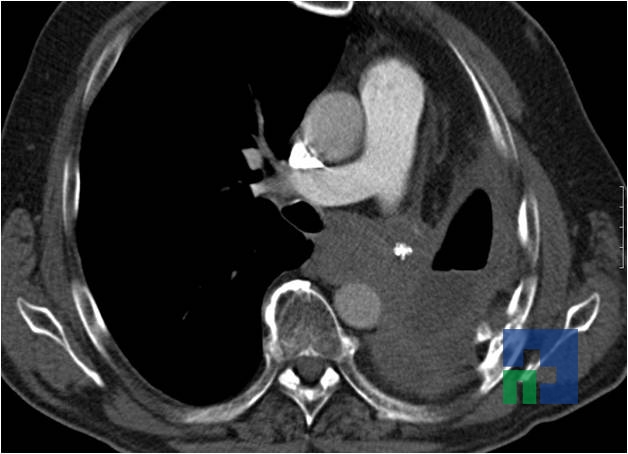

- Fistula carotido-cavernoasa